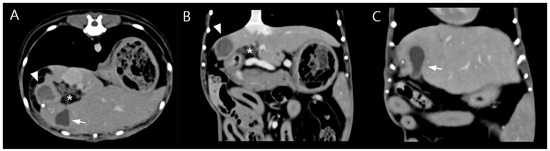

Abdominal ultrasonography showed progressive gallbladder wall thickening, localized hyperechoic peritonitis, and a heterogeneous hepatic nodule with internal anechoic, cyst-like structures (Figure 1), raising suspicion for hepatic abscess, cholangitis, or hepatitis. Concurrently, ultrasound-guided fine-needle aspiration (FNA) and bacterial culture with antibiotic susceptibility testing were performed. Grossly, the aspirated material was yellowish and slightly turbid, with a viscous, bile-tinged appearance consistent with a septic inflammatory process. Cytologic analysis of the FNA sample revealed numerous toxic neutrophils (Figure 2), and the hepatic nodule was diagnosed as a hepatic abscess.

Figure 1.

(A) Abdominal ultrasonographic image showing the liver and gallbladder. The gallbladder wall is thickened (arrow), displaying a double rim sign, which can be seen in cases of gallbladder edema, hypoalbuminemia, sepsis, or peritonitis. A region of increased echogenicity is present dorsal to the gallbladder (asterisk), suggestive of localized peritonitis. A heterogeneous hepatic nodule is also identified (arrowhead). (B) The hepatic nodule (arrowhead) appears round but atypical, containing internal septations and anechoic cyst-like structures. Increased echogenicity of the adjacent peritoneum beneath the nodule (asterisk) is noted, consistent with peritoneal reaction.